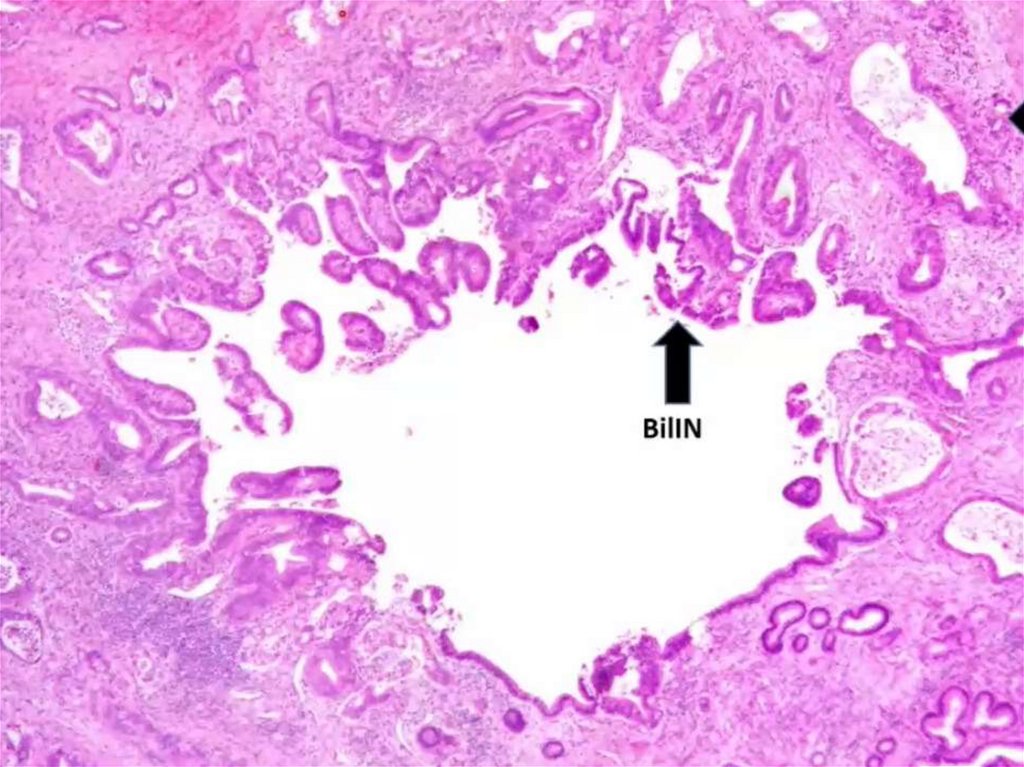

Cholangicarcinoma